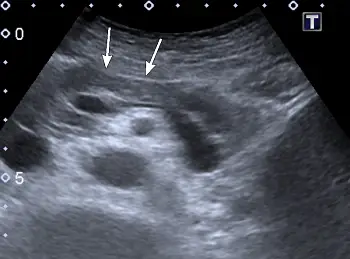

附圖為上腹部橫向掃描之超音波影像,箭號所指為何?

本圖為上腹部正中橫向掃描 (Transverse scan) 的典型超音波影像。由深層(影像下方,靠近背部)到淺層(影像上方,靠近腹壁探頭處),我們可以依序辨識出以下經典解剖構造:

- 腹主動脈 (Aorta):影像最下方深處的圓形無回音 (anechoic) 構造。

- 上腸繫膜動脈 (Superior Mesenteric Artery, SMA):位於腹主動脈前方,呈現一個較小的圓形無回音構造,其周圍通常被高回音 (echogenic) 的後腹腔脂肪組織包圍。

- 脾靜脈 (Splenic Vein):位於 SMA 的前方,是一條橫向走行的長管狀無回音構造,這是在超音波下尋找胰臟最重要的解剖指標。

- 胰臟 (Pancreas):位於脾靜脈正前方,呈現一條回音度中等、略高或等同於肝臟實質的帶狀構造。圖中兩個白色箭號正是指向這個帶狀構造的體部 (Body of pancreas)。

- 肝臟左葉 (Left lobe of the liver):位